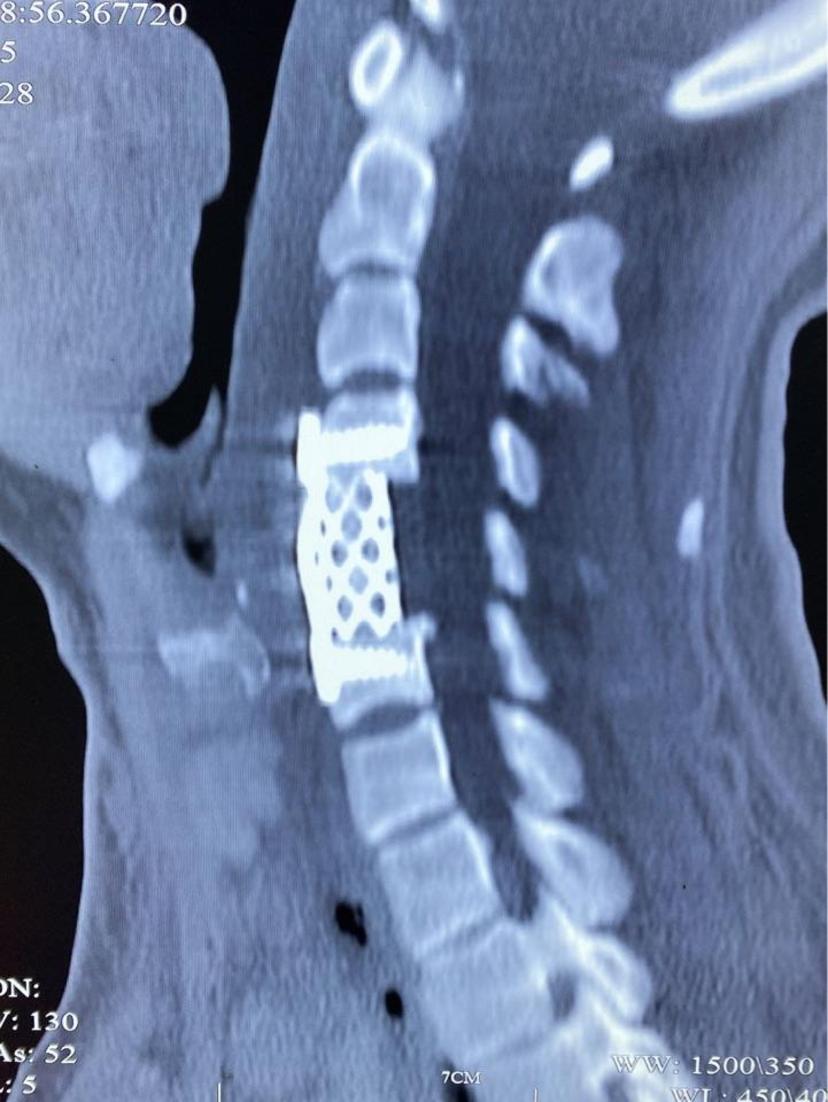

CT显示减压充分,致压物完全去除,生理曲度恢复

位置良好